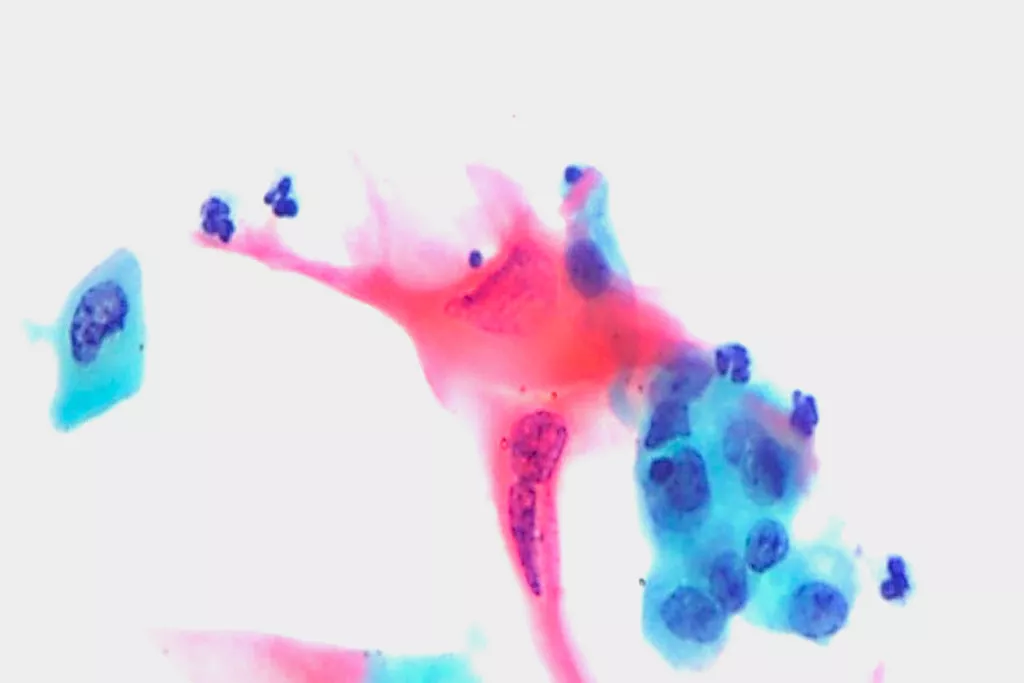

Galerie d’images9

9. Images reçues du service de cytopathologie, hôpital Llandough, Pays de Galles